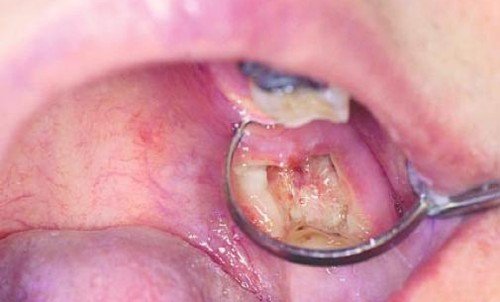

Альвеолит — это болезнь, что связано с воспалением лунки челюсти, как итог ее инфицирования после травматического вырывания зуба. При всем этом нередко находится повреждение самой лунки и раздавливание десны, что его окружает. Оно может развиться и в следствии несоблюдения послеоперационного режима, другими словами когда постоянным полосканием рта промывают тромб из лунки, при всем этом бактерии попадают в нее и вызывают воспаление. Также попадание еды в лунку, и некорректная гигиена полости рта тоже служит появлению альвеолита.

Исцеление состоит из последующих шагов: выскабливают лунки, обрабатывают их веществом перекиси водорода либо протеолитическими ферментами, и конечно делают дренирование. Нередко делают и повторное выскабливание. При всем этом прописывают амидопирин, анальгин, физиотерапию. И в конечном итоге прогноз становится довольно подходящий, и нетрудоспособность порядка 2-3 дней. Бывает, что луночные боли продолжаются в протяжении 2-3 недель. Профилактикой служит атравматичное удаление зуба.